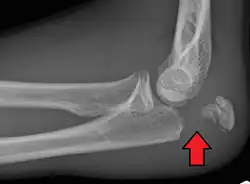

To assess an olecranon fracture, a careful skin exam is performed to ensure there is no open fracture. Then a complete neurological exam of the upper limb should be documented.[5][2] Frontal and lateral X-ray views of the elbow are typically done to investigate the possibility of an olecranon fracture.[1] A true lateral x-ray is essential to determine the fracture pattern, degree of displacement, comminution, and the degree of articular involvement.

Tension band fixation is the most common form of internal fixation used for non-comminuted olecranon fractures.[5] It is typically reserved for noncomminuted fractures that are proximal to the coronoid.[2] This procedure is performed using Kirschner wire (K-wires) which converts tensile forces into compressive force.[2]